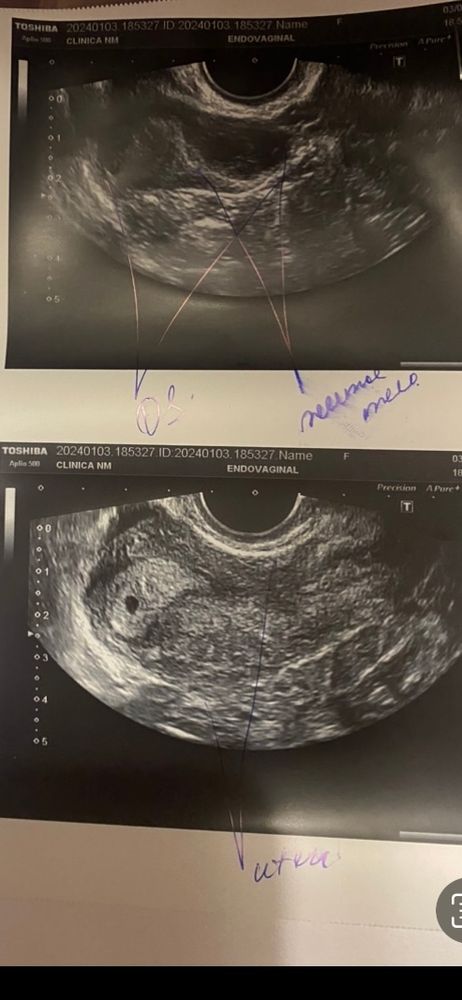

Овуляция была +-15 декабря по тестам. 26 декабря (11 дпо) тест на беременность показал две полоски и хгч 48. 03.01.2023 (19 дпо) ну узи увидели плодное яйцо 4мм и поставили 2 н от зачатия. Сказали сдать хгч 04.01.2024 (20 дпо) 3394 хгч. По калькуляторам быстры рост. Начинаю переживать